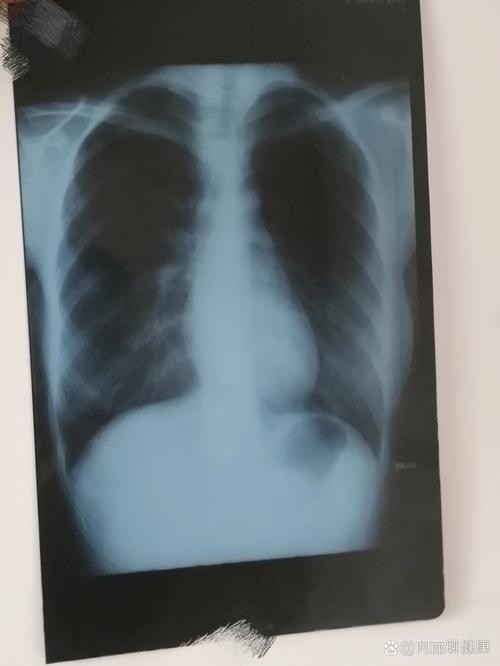

(图片来源网络,侵删)- 这个阶段,受精卵刚刚着床,细胞处于快速分裂期。